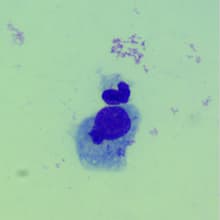

진료사례4개월 먼치킨 : 결막염 치료

4개월된 먼치킨 고양이가 옥길아라동물치료센터에 내원했습니다. 아이는 심한 결막 부종, 눈물, 눈곱 증상이 있어 보호자분과 함께 내원하였습니다. 원인을 찾기 위해 도말 검사를 진행하였습니다. 도말 검사 결과 봉입체로 생각되는 양상이 다수 발견되어, 클라미디아 결막염으로 진단되었습니다. 이에 맞는 항바이러스 안약 및 적절한 항생제를 투여 조치 하였고, 집에서 관리가 가능하도록 자세히 안내드리고 모니터링을 진행하였습니다. 치료 진행 2주뒤, 아이의 눈은 깨끗하게 회복되었고, 건강한 눈으로 활동하고 있는 것을 확인할 수 있었습니다.